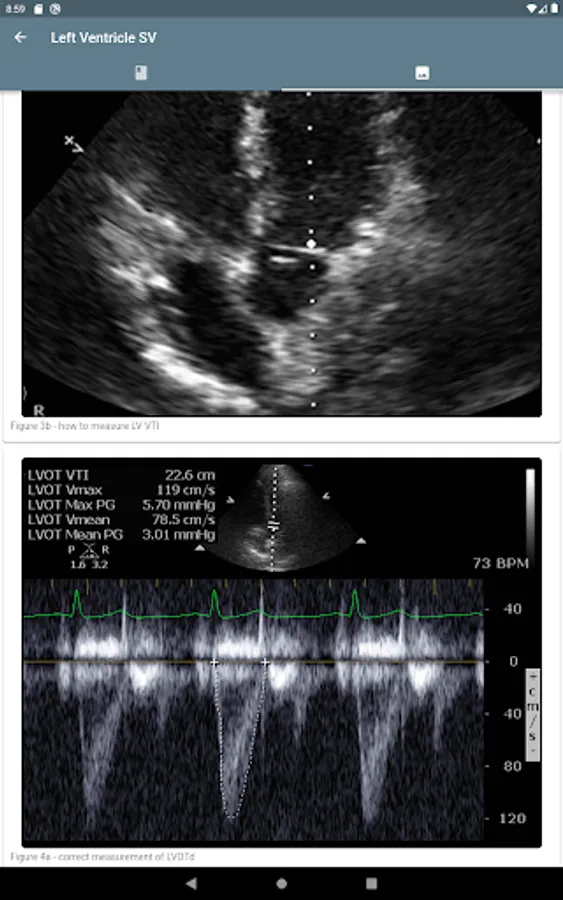

Use the calculators to get the cardiac output, stroke volume, systemic vascular resistance, inferior vena cava respiratory variation, and other metrics. The educational content can be accessed from the calculator so that the learning continues.